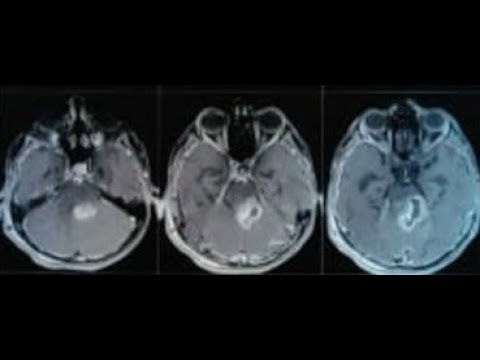

Hellow guys, Welcome to my website, and you are watching Tectal plate glioma with hydrocephalus with CSf rhinorhoea from lat sphenoid recess. and this vIdeo is uploaded by Dr K K Bansal at 2022-09-09T11:30:46-07:00. We are pramote this video only for entertainment and educational perpose only. So, I hop you like our website.